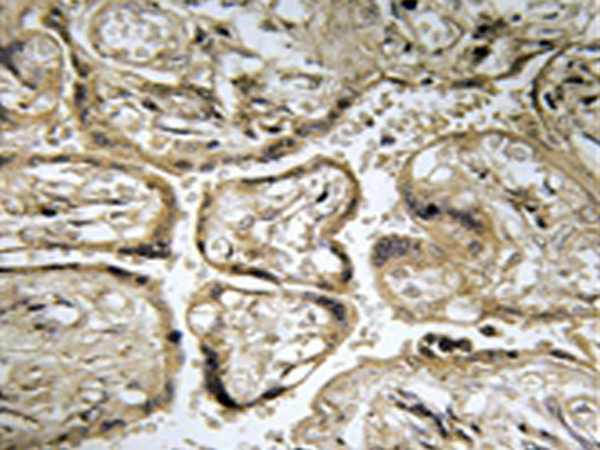

IHC |

IHC positive control: |

Human placenta tissue |

IHC Recommend dilution: |

50-100 |